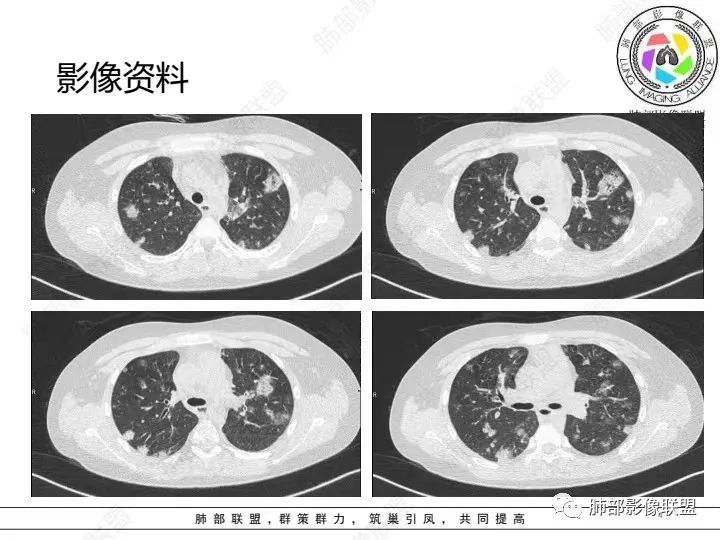

少年患者,游泳后发热畏寒,呼吸困难,两肺弥漫分布结节及磨玻璃影,考虑寄生虫感染,钩体病?

外伤后与河水接触史,病灶分布随机,点晕征,淋巴低,CRP、降钙素高。休克血压。考虑感染性病变:钩端螺旋体病

两肺散在磨玻璃影,靠近胸膜多见,边缘有晕征,考虑感染性疾病,真菌感染

青少年,双肺多发结节斑片影,肝密度减低,有下水的经历,PCT太高,考虑感染性疾病,钩体病?金葡菌脓毒性栓子?

患者河里游泳,受伤,发热,血压低到休克,呼吸困难三凹征,血气提示呼吸性碱中毒合并代谢性酸中毒且代酸占上峰,肺部表现既无明显出血的磨玻璃影(不符合钩体导致出血的特征)又无多发影内空洞(这点不符合金葡菌),是真菌感染的影像,河水属污水,故肺部表现为:尖端赛多孢子肺炎(这个菌感染重,死亡率高)!

青少年,高处跳落游泳史,左侧盆部疼痛(怀疑皮肤损伤),畏寒发热,CRP和Pct显著升高,感染性休克表现(提示革兰阴性杆菌),双肺叶外周分布为主棉絮状结节及斑片影,GGO密度,边缘清,间质及实质改变,病灶内细网格影,见供血血管证,分布特点双肺叶Spe表现,考虑大肠杆菌导致血行感染,血培养检查!

男14岁,2天前下河游泳史,发热;两肺近外带可见磨玻璃密度影,边缘疑似晕征,结合实验室检查,符合感染,倾向真菌感染,支持肺钩端螺旋体病。

青少年,2天前下河游泳后畏寒发热,两肺外周胸膜下分布多发大小不等结节、斑片及磨玻璃,边缘模糊,考虑血流性感染,钩体?金葡?

青少年男性,2天游泳后发热,双肺多发斑片状,结节状阴影,多分布肺外带,血道来源,部分病灶边缘可见磨玻璃影,患者有明显脂肪肝病史,考虑.感染性病变,金黄色葡萄球菌?钩体?肺克?

青少年,河沟游泳后急性发病,左侧髋部疼痛,双肺弥漫地方结节、斑片模糊影,CRP、PCT明显增高,考虑钩体病,鉴别血播金葡

PCt>200,脓毒血症了,有无皮肤损伤?诱因游泳,高处跳水,与水有关,影像为多发毛玻璃结节,有细网格样改变,内可见支气管影,所以是间质改变➕肺泡渗出;结节分布是随机分布,血源性。与临床相对应。感染性病变,pct不支持病毒排除。细菌,金葡?军团?需复查看看病情转变。有无三红三痛,如有,钩也可能。寄生虫待排。

急性起病,游泳史,寒战发热,感染指标明显升高,胸部CT双肺多发磨玻璃影,实变,内可见支气管扩张,大致呈间质改变,随机分布,首先考虑感染性疾病。

年轻患者,急性起病,高处跌下,皮肤损伤,两肺胸膜下多发实变,边缘见磨玻璃影,部分实变呈楔形,实变内见粗网格影,部分实变见反晕征,综和病史考虑感染性病变,影像上符合脓毒性肺栓塞,支持血源性金葡菌感染,鉴一下COP

青年人,有游泳史,畏寒发热,双肺内及胸膜下多发实变,边缘见磨玻璃密度影,部分呈反晕征,内可见多发网格样改变,考虑感染性病变,金葡菌感染

双肺叶结节及斑片状磨玻璃样密度,边缘清,外周分布为主,部分见供血血管,分布特点符合Spe表现,青少年,高处跳落游泳史,左侧盆部疼痛,畏寒发热,CRP和Pct显著升高,考虑血行感染,金葡?至于大家考虑的钩端螺旋体病和嗜水单胞菌不是太了解

青少年发病急,高热,双肺多发斑片状磨玻璃影,边界模糊,以胸膜下为主,考虑感染性病变,金葡菌可能

青年,游泳,盆骨处疼痛”原因?”,畏寒,发热,Pct明显升高。双肺多发斑片,结节影。胸膜下也有。考虑血播。金葡可能大

游泳,高处跳下盆骨疼痛,肺上血播及气道均有,符合感染性病变,吸入性病变,金葡菌肺炎要考虑

分布,胸膜下和支气管束分布 密度以磨玻璃为主 ➕小叶内间隔增厚细网格征 出血?病毒性感染?

男,14岁,高处跳下,游泳后畏寒。胸部CT:两肺多发斑片影、结节影;沿支气管血管束分布,胸膜下也有;密度以GGO为主,部分为mGGO;边缘部分清楚,大部分模糊;内可见网格影、支气管充气征。考虑:SPE?肺水肿?鉴别淋巴瘤。

2.影像上肺多发混合密度片影,随机分布,胸膜下分布优势,病灶边界大多隐约可辨,偏柔和,动脉血管影穿行,未见钙化、液化空洞、或明确气囊影,未见树芽征。

3.双侧胸腔未见积液。双肺门及纵隔未见增大淋巴结。

4.肝左右叶密度减低,未见结节影、块影或液化区。

3.影像方面:双肺多发病灶,随机分布,且有相当部分沿胸膜下,是可以符合血流感染的。

1.外围分布,胸膜下为主,两肺弥漫结节或胸膜下楔形影,边界清,周围伴有GGO